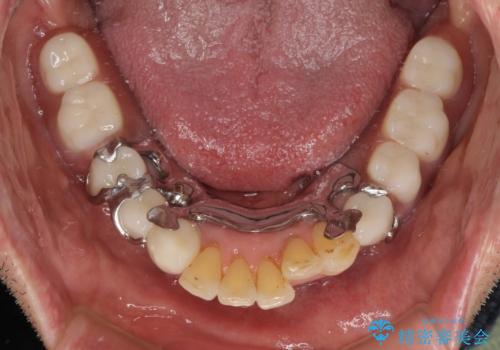

自費治療の義歯は装着感がとても良いですが、急に入れ歯を装着すると、異物感が強く継続使用できなくなるため、仮歯の期間中に保険治療での義歯を装着してもらい、口腔内を義歯に慣れさせるようにしました。

より適合の良い義歯とするため、セラミッククラウンなどは義歯の設計に合わせた土台の歯となるよう全て再製作をし、安定感に優れた義歯を製作することができました。